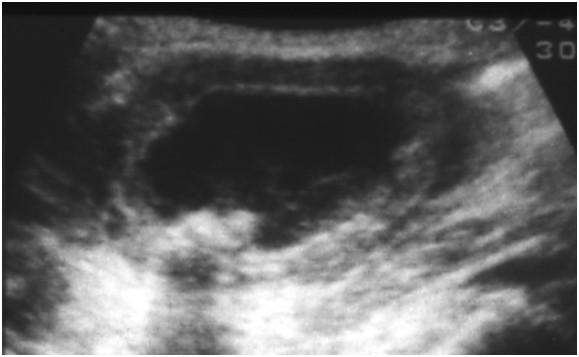

• 胆嚢炎の超音波画像診断のすべて

超音波スキャンは、医師が胆嚢炎を診断するために使用する主な検査の 1 つです。スキャン検査により、医師はこの症状の原因となる胆石の存在を発見できる場合があります。

胆嚢炎は胆嚢の炎症です。通常、胆石が胆嚢の開口部に詰まったときに発生します。

医師が胆嚢炎の可能性があると判断した場合、超音波検査を受けることがあります。

胆嚢の超音波検査は、胆嚢疾患の兆候を最初に検査するのに最適な画像検査です。臨床医は胆石炎症が存在するかどうかを確認できます。

臨床医は、その速度、アクセスしやすさ、および放射線の不足により、 CT スキャンなどの他の画像形式よりも超音波を好みます。

超音波検査は胆石の表示に適していますが、医師が血液検査身体検査と併用すると、胆嚢炎の診断に最も役立ちます。

超音波検査では、胆嚢炎に関連する多くの要因を見つけることができます。これらには次のものが含まれます。

• 胆石

• 胆嚢の肥大

• 胆嚢壁の肥厚

• 胆嚢の周囲に体液が蓄積すること

これらの兆候の存在は、胆嚢炎の診断に役立ちます。

超音波は、胆嚢開口部の胆石を特定し、マーフィー徴候を観察するのに最も正確です。結果として、これらは超音波検査者が胆嚢炎を診断するために探す主な所見となります。